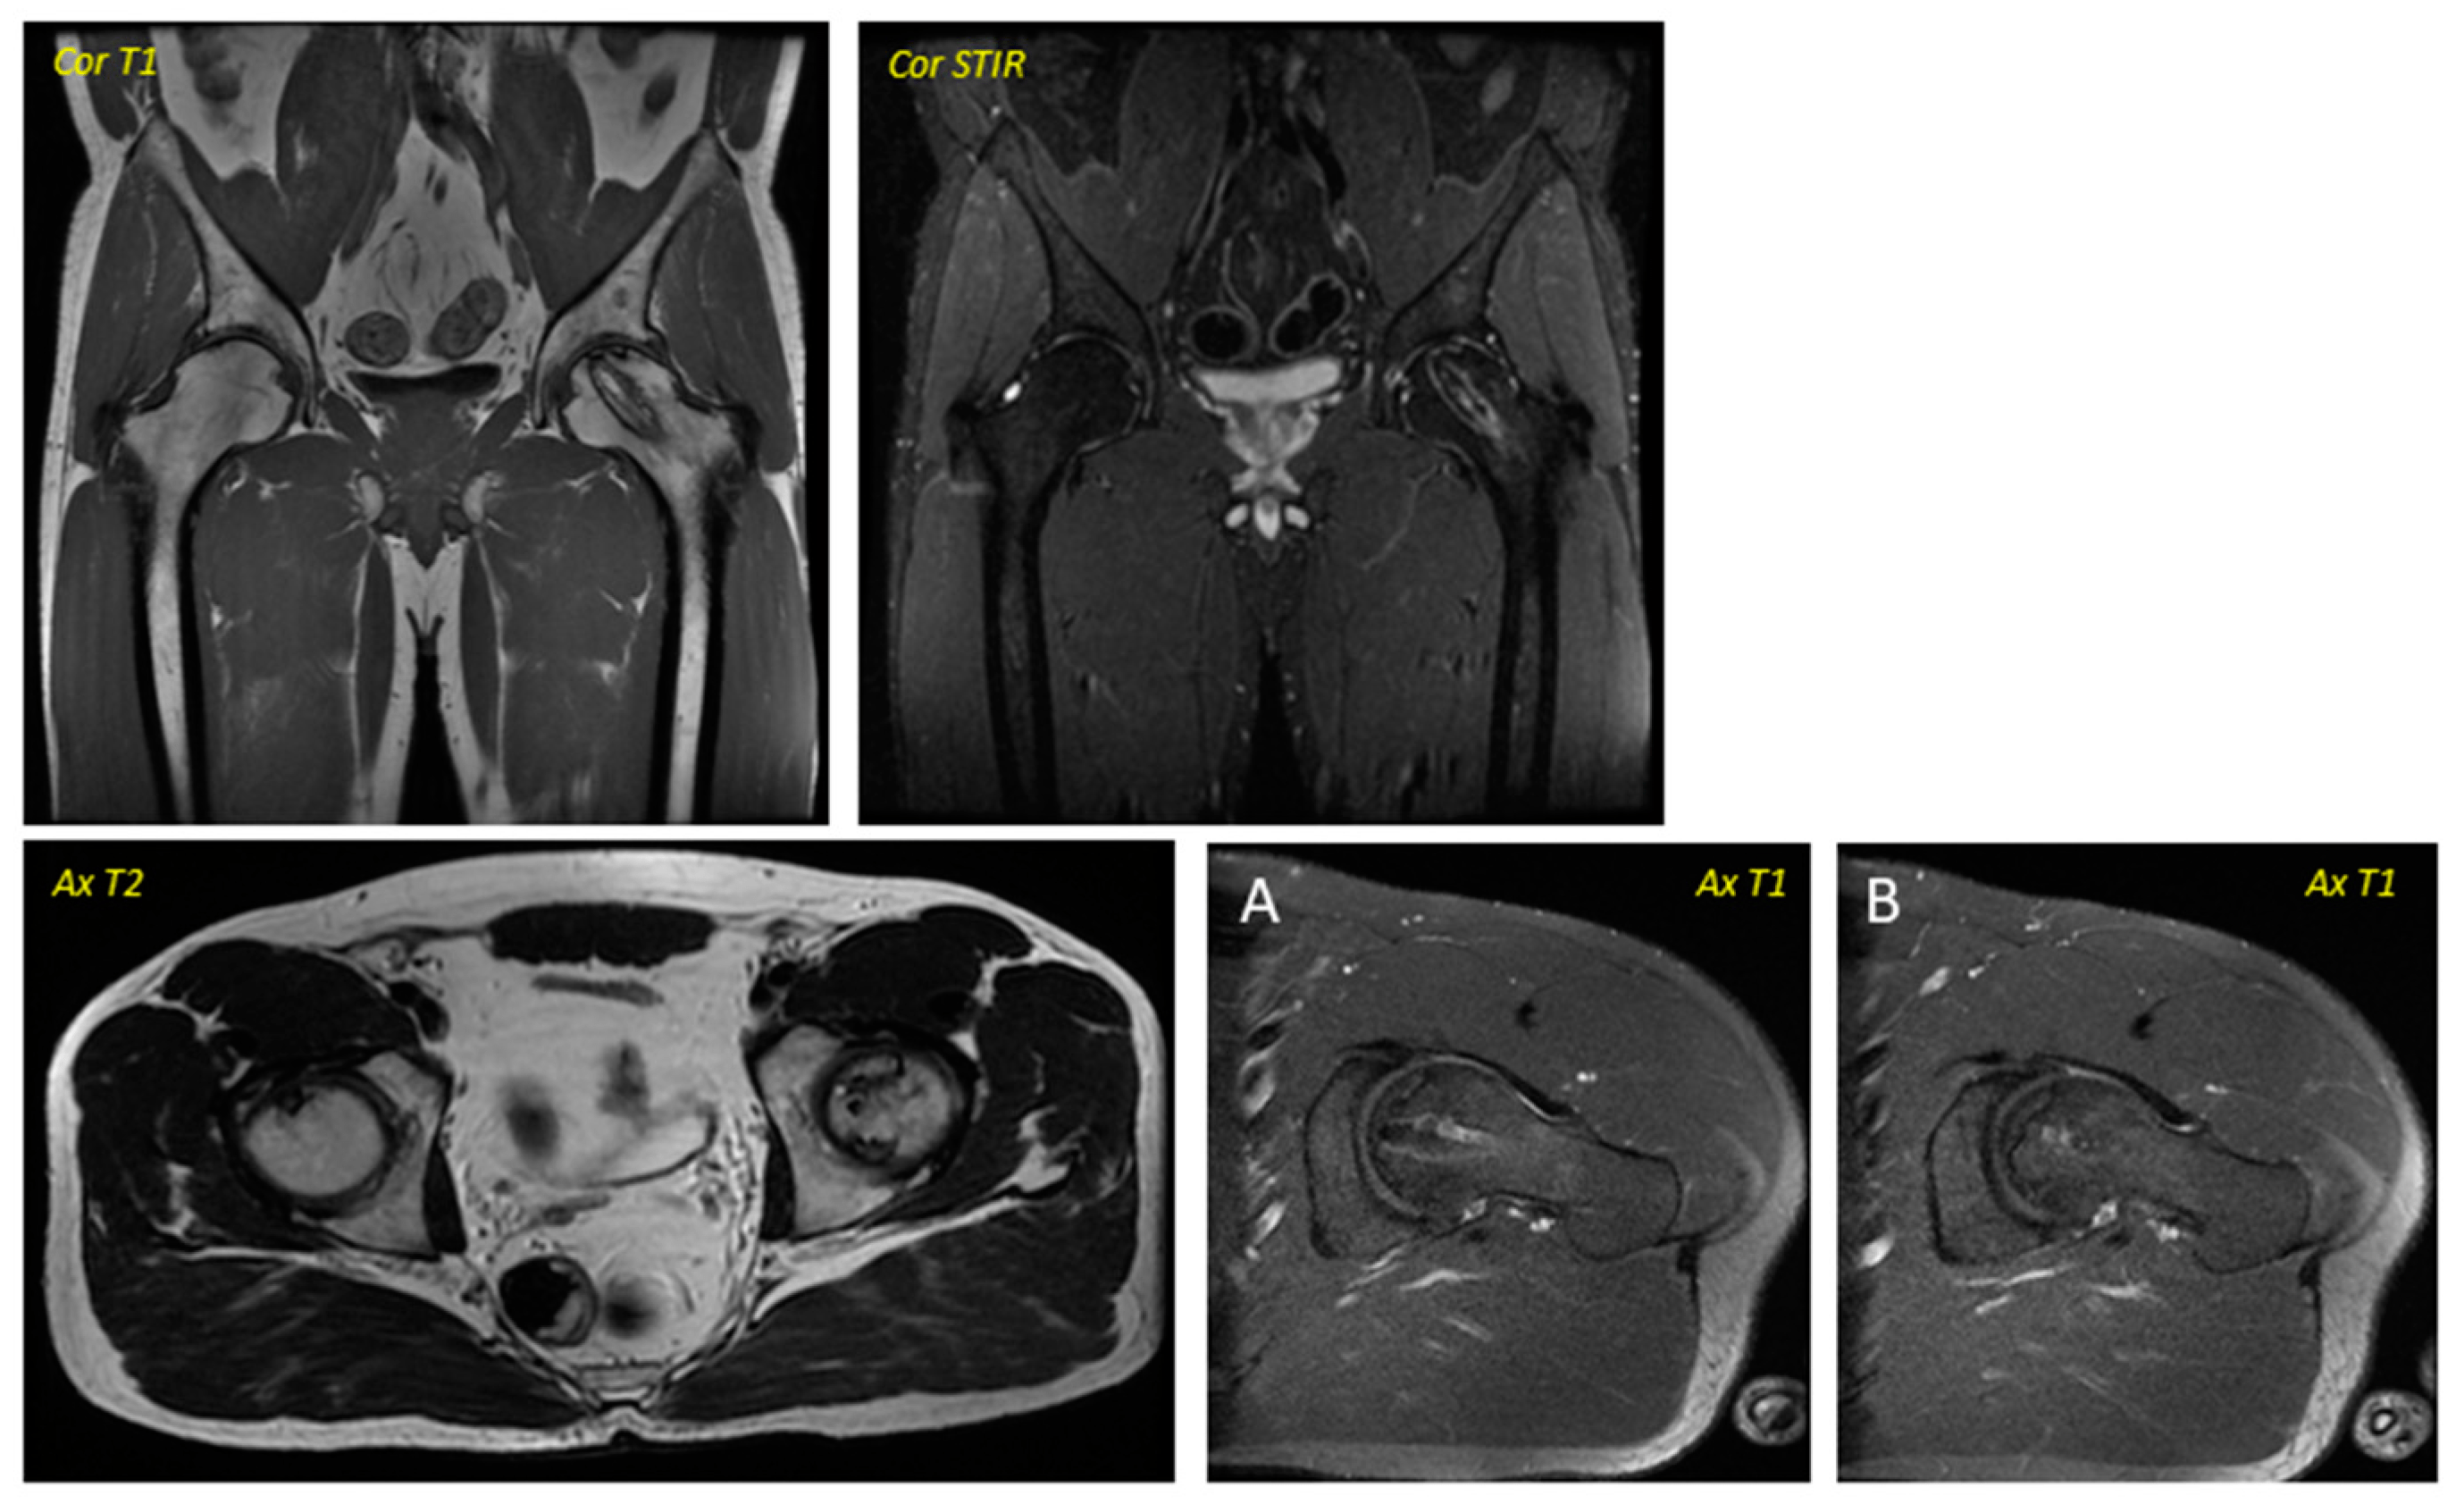

關(guān)于影像學(xué)研究,在12個月的隨訪期間,在影像學(xué)演變中觀察到了一些發(fā)現(xiàn)(圖1和圖2)。

首先,方向的變化從第六個月開始出現(xiàn)在所有病例中,而在早期階段并不明顯。其次,62.5%的患者 ( n=5) 在手術(shù)后的第一年內(nèi)實現(xiàn)了影像穩(wěn)定。第三,兩名患者 (25%) 出現(xiàn)壞死區(qū)進展,而一名 (12.5%) 患者出現(xiàn)明顯的再骨化跡象。盡管觀察到描述性差異,但后一個參數(shù)的p值在統(tǒng)計學(xué)上并不顯著。